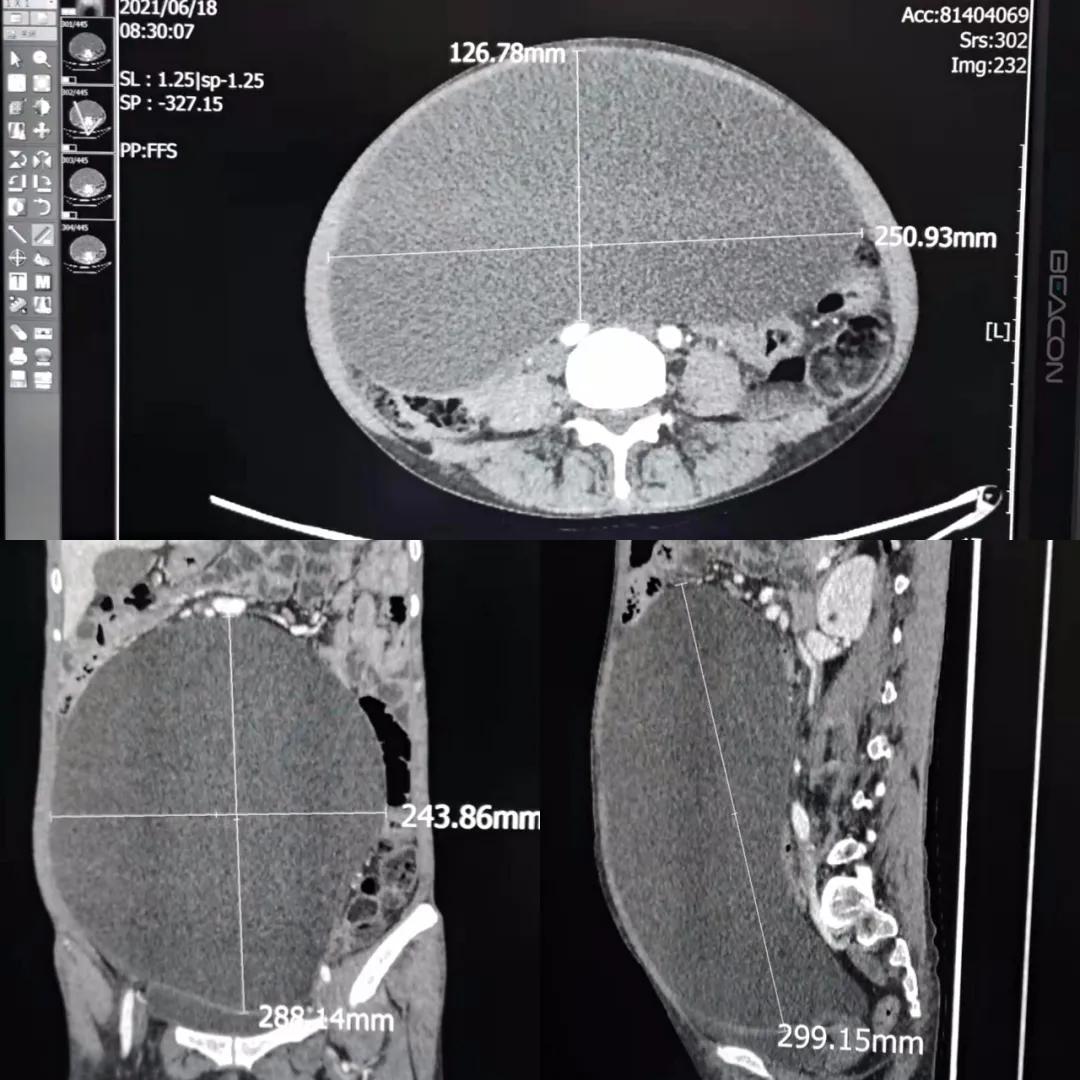

外科李智主任仔细询问了患者的病史并仔细查体后,安排患者住院检查,不查不知道,一查吓一跳,张阿姨长了一个巨大的囊液瘤,大小竟然达到25×15×30cm。由于这个瘤子太过于巨大,不但造成患者身体负担过重,消瘦,活动受限,同时也导致了她血液中白细胞、血小板和红细胞等重要成分的显著降低,不到正常的三分之一,都达到了“危急值”,很容易诱发感染、出血等情况,给手术治疗带来极大的风险。